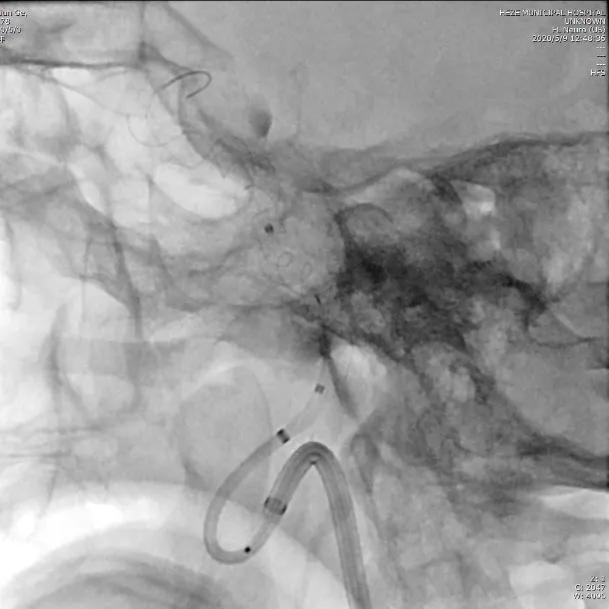

检查:经颅脑MR平扫+MRA检查考虑右侧海绵窦段动脉瘤。在局麻下行DSA,结果示:右侧颈内动脉海绵窦段动脉瘤;右侧颈内动脉C1段严重迂曲;右侧大脑中动脉M1段中度狭窄。

术前测量:动脉瘤大小为12x11mm,瘤颈为13mm,动脉瘤远端血管直径3.8mm,近端血管直径4.5mm。

选择5.0×45mm Tubridge®支架,成功释放,覆盖动脉瘤,造影见动脉瘤腔内造影剂明显停留。